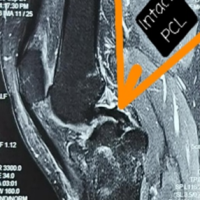

Magnetic resonance imaging (MRI) scan was performed to better delineate the associated other ligaments and chondral injuries (Fig. 2).

Figure 2: Pre-operative magnetic resonance imaging sagittal images showing posterior cruciate ligament avulsion fracture with Hoffa fracture.